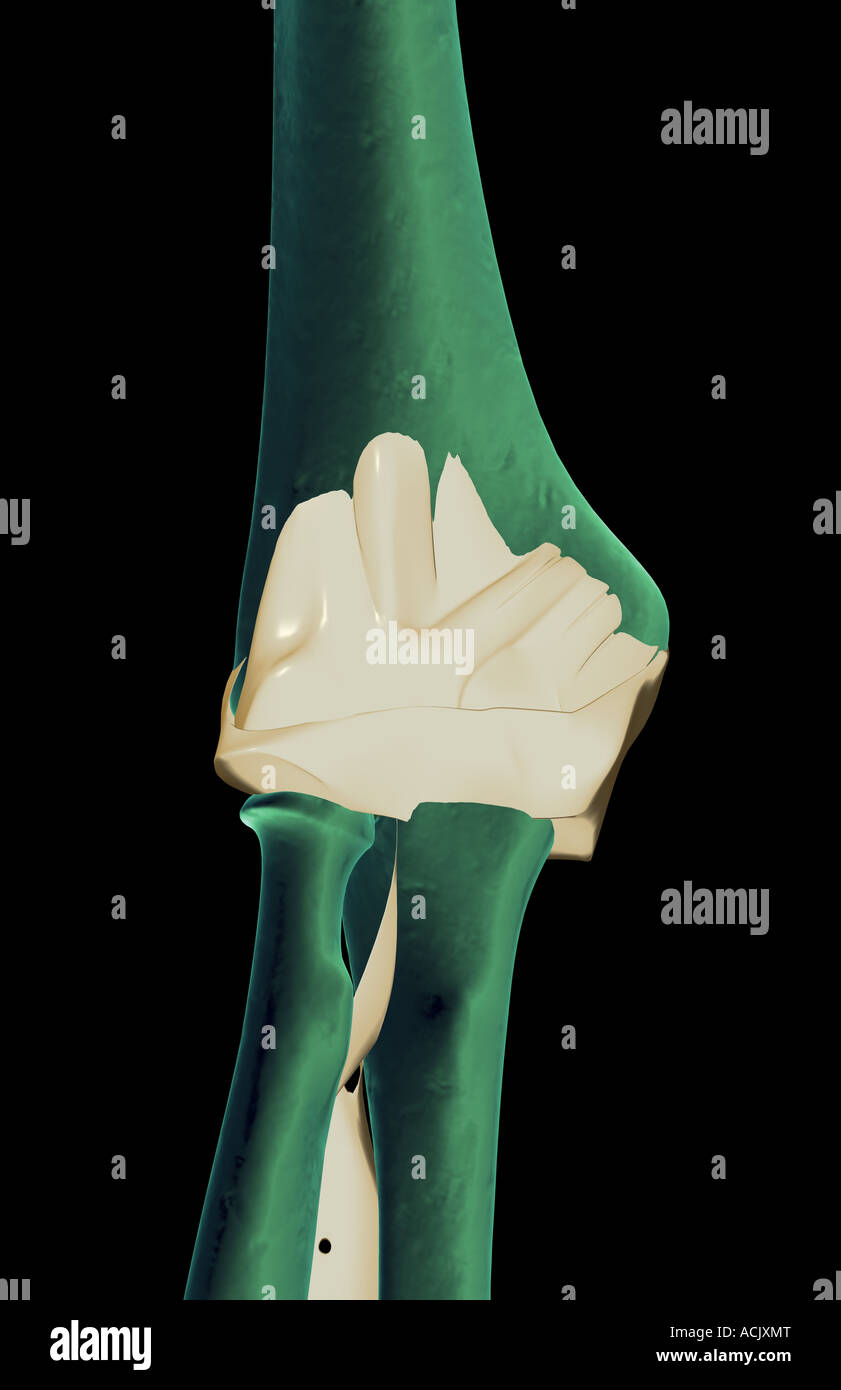

The ligaments of the elbow Stock Photohttps://www.alamy.com/image-license-details/?v=1https://www.alamy.com/stock-photo-the-ligaments-of-the-elbow-13173911.html

The ligaments of the elbow Stock Photohttps://www.alamy.com/image-license-details/?v=1https://www.alamy.com/stock-photo-the-ligaments-of-the-elbow-13173911.htmlRFACJXMT–The ligaments of the elbow